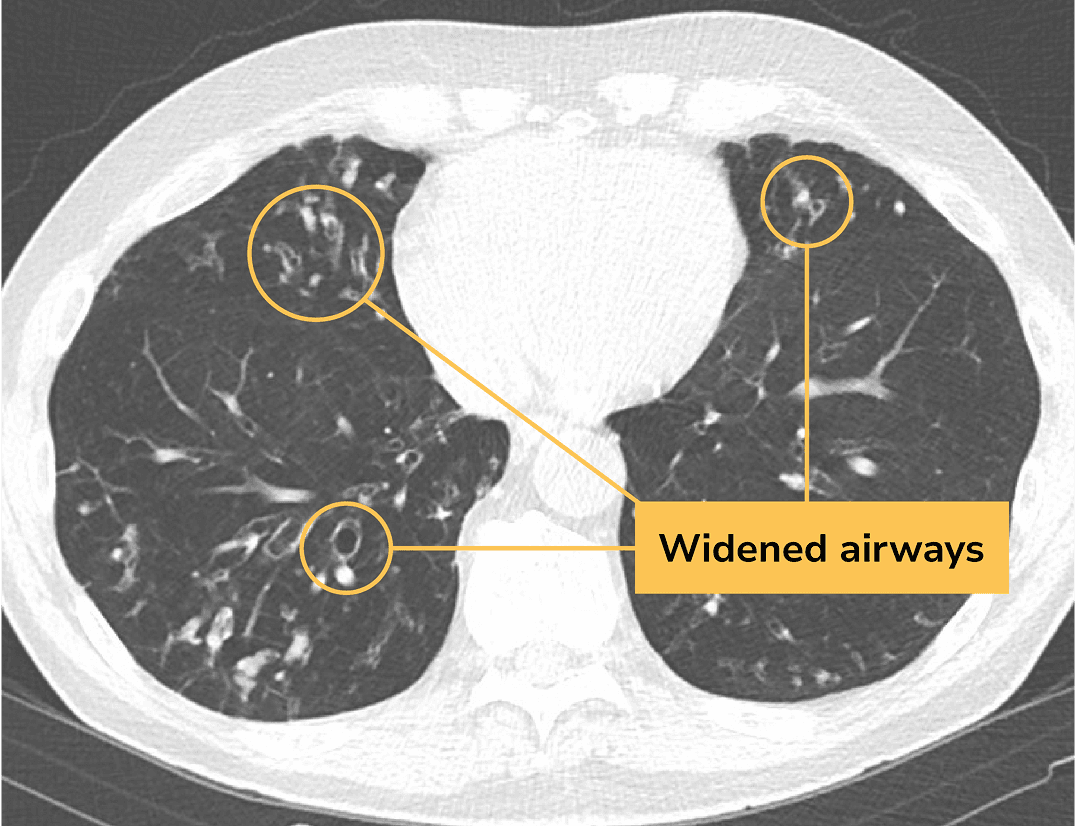

A CT scan is a type of chest scan that provides clear, detailed images of the lungs. It’s used to diagnose BE because it can reveal widening of the bronchi—a sign of the disease that tests like an X-ray might miss.

A CT scan of a lung with bronchiectasis